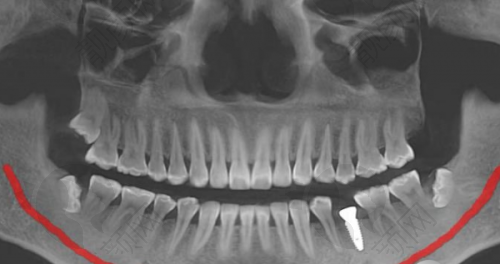

像全口/半口即刻种植、即刻修复、穿颧穿翼种植牙,这些复杂的手术,不是每一家医院都能做得好。但鼎植口腔潜心研究并进行VIIV颧骨种植和穿翼板种植、全口/半口即刻种植、即刻修复,还积累了特别多成功的例子。

比如说VIIV颧骨种植技术,它可用于上颌骨重度骨吸收情况下的口腔种植,不用植骨,也不用长时间等待,而且微出血。这项技术突破了传统种植牙对牙槽骨条件的限制,能为缺骨的患者实现即刻种植、即刻负重。鼎植口腔还把改良颌外颧骨种植技术和VIIV整体解决方案用到临床上,成效非常好。

王先生因为骨头条件差,长期缺牙,吃饭都成问题。后来在鼎植口腔做了穿颧种植全口修复,终于能正常吃饭了。他对鼎植口腔的技术和服务都给予了高度评价,觉得鼎植口腔解决了他的大难题。